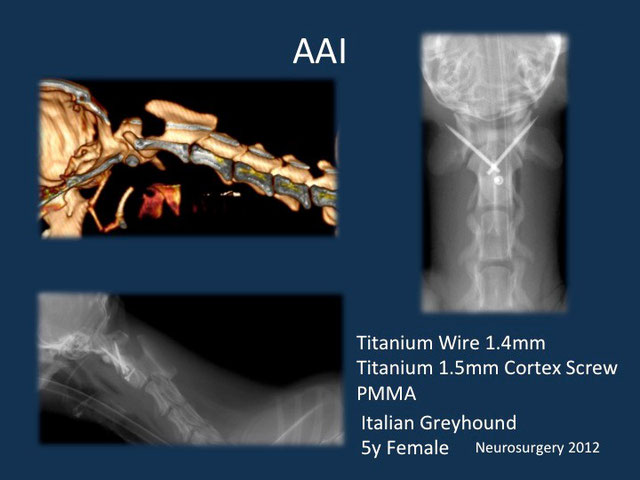

環軸不安定症 AAI

AAIとはヨークシャーテリア、チワワなどの超小型犬に発症する第一頚椎と、第二頚椎の不安定性による頸髄の障害です。通常、頚部痛、四肢不全麻痺などの症状がでます。

悪化すれば呼吸停止により突然死することもあります。